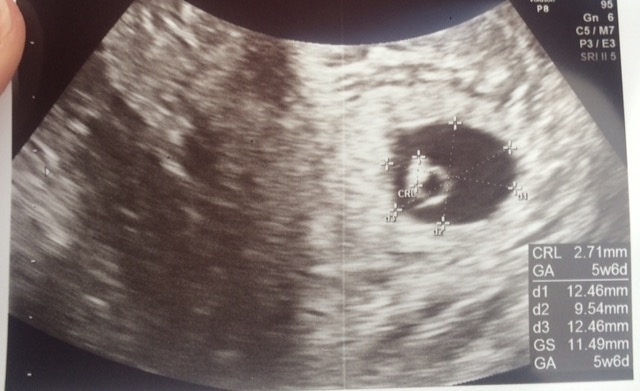

We got to see our little sweet pea this morning and my husband who I have only seen cry twice in our 8 years together teared up when we saw the little heartbeat flickering!! It was so awesome. Everything is great! He or she is 2.7 mm.